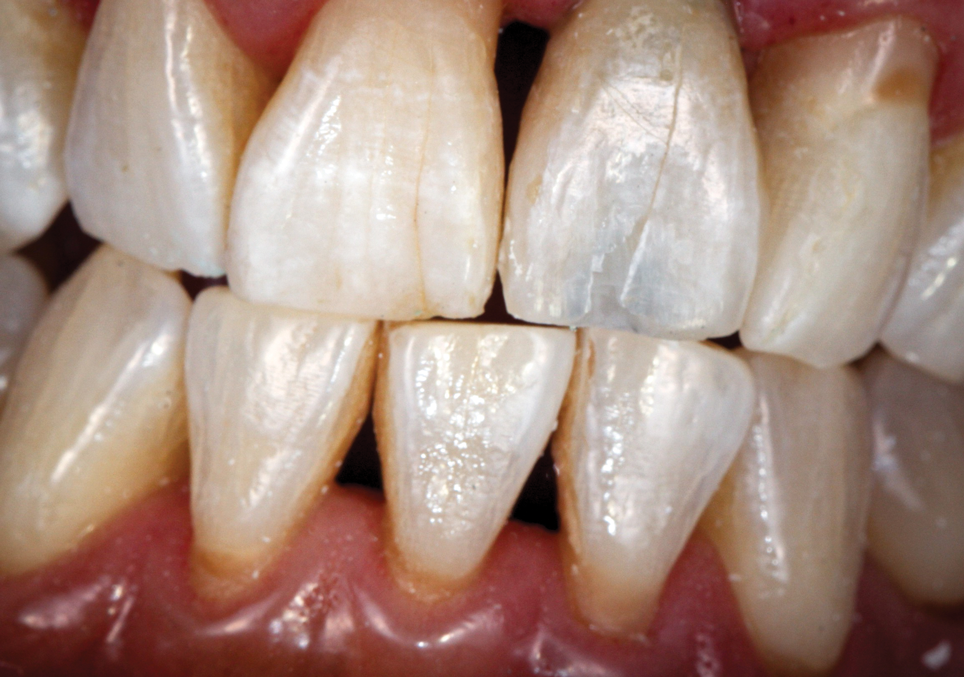

The immediate replacement of a single missing tooth with a dental implant in the esthetic zone is among the more challenging scenarios faced by clinicians. As such, it requires special attention to planning and execution at each stage of treatment and often necessitates the modification of "standard" implant workflows. The delivery of a provisional restoration immediately following placement of an implant and graft materials is justified and advantageous when specific criteria are met.1-4 Immediate provisonalization protocols are not appropriate for every implant site; therefore, the careful consideration of key risk criteria is essential to case selection and to improve the prognosis and predictability (Table 1). For example, implants with low primary stability, such as those with insertion torque values less than 20 Ncm or implant stability quotient (ISQ) values less than 60, as well as a high occlusal or functional load, a lack of buccal bone, or the presence of active periodontal disease are all factors that increase the risk of a poor prognosis for immediate provisionalization protocols. Implants with a high primary stability of greater than 30 Ncm or an ISQ value greater than 65 decrease the risk of a poor prognosis for immediate loading protocols. Other factors that decrease the risk of a poor prognosis include low functional loads, the presence of sufficient buccal bone, and implants that are placed 3 to 4 mm below the intended cementoenamel junction (CEJ).

Patient and Site Selection

Successful management of the esthetic zone with immediate implant provisionalization requires specific conditions regarding the patient's occlusion and oral health as well as for the recipient bed. To immediately provisionalize an implant in the esthetic zone, the patient's periodontal health should be ideal, the occlusion should be normal (eg, no deep bite), and there should be no signs of grinding/bruxism. Requirements for the recipient bed include the absence of inflammation or other pathoses, an intact alveolar socket on the labial aspect, sufficient bone width and height to permit adequate initial implant stability, and healthy gingiva.